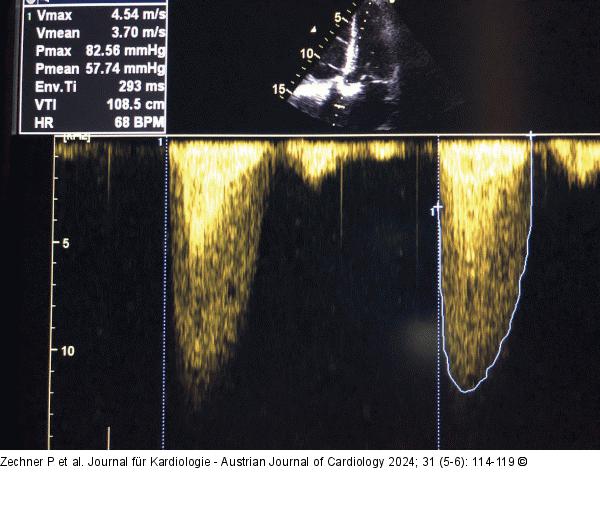

Abbildung 4: CW-Doppler - Overgain CW-Doppler: Aortenklappenstenose. Es handelt sich um den gleichen Patienten wie bei Abb. 3, aber jetzt bei dunklem Hintergrund; ohne „Overgain” viel geringere VTI. |

CW-Doppler: Aortenklappenstenose. Es handelt sich um den gleichen Patienten wie bei Abb. 3, aber jetzt bei dunklem Hintergrund; ohne „Overgain” viel geringere VTI. |